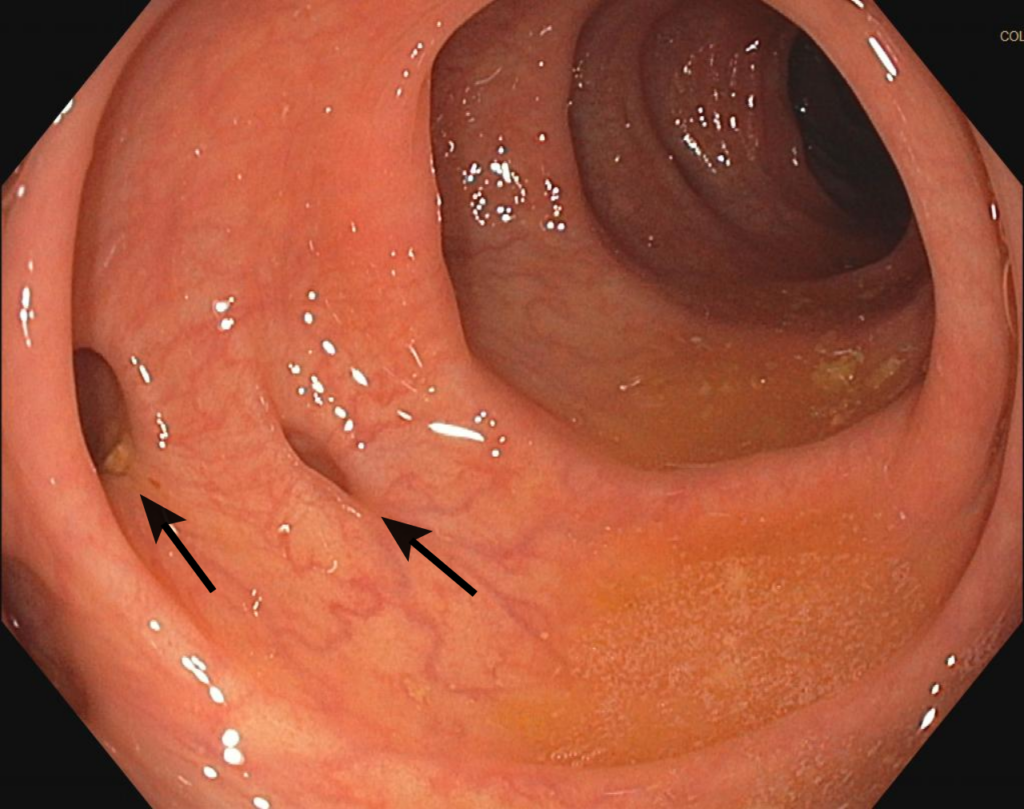

Choroba uchyłkowa jelit to stan, w którym w ścianie jelita grubego tworzą się niewielkie wypukłości, zwane uchyłkami. Zazwyczaj jest bezobjawowa, ale może prowadzić do zapalenia (uchyłkowatość) lub zakażenia (zapalenie uchyłków), powodując ból brzucha, gorączkę i zaburzenia trawienne. Częstość występowania wzrasta z wiekiem i jest związana z dietą ubogą w błonnik. Leczenie może obejmować zmianę diety, leki, a w ciężkich przypadkach, interwencję chirurgiczną.

Gastroenterologia to dział medycyny zajmujący się diagnostyką i leczeniem chorób układu pokarmowego. Specjaliści w tej dziedzinie, zwani gastroenterologami, badają schorzenia związane z przełykiem, żołądkiem, jelitami, wątrobą, trzustką oraz pęcherzykiem żółciowym. Gastroenterologia obejmuje zarówno choroby zapalne, takie jak zapalenie jelita grubego, jak i zaburzenia funkcjonalne, takie jak zespół jelita drażliwego. W ramach gastroenterologii wykonuje się różnorodne procedury diagnostyczne, takie jak endoskopia, kolonoskopia czy ultrasonografia, które pozwalają na ocenę stanu narządów pokarmowych oraz wykrywanie ewentualnych patologii. Leczenie schorzeń układu pokarmowego może obejmować zarówno farmakoterapię, jak i interwencje chirurgiczne, w zależności od rodzaju i ciężkości choroby. Gastroenterologia odgrywa kluczową rolę w utrzymaniu zdrowia układu pokarmowego i poprawie jakości życia pacjentów z problemami trawiennymi. >>>